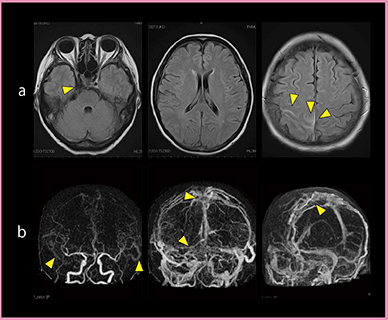

症例1は,激しい頭痛と動眼神経麻痺で来院した50歳代女性で,MRIのFLAIRでは右海綿静脈洞内に内頸動脈以外にflow voidが見られた。右頭頂葉皮質から皮質下と両側前頭葉皮質の一部,上矢状静脈洞内に高信号が認められ,静脈洞血栓症を疑った(図4a)。4D-CTA(図4b)では,動脈相から肥大した皮質静脈が早期に出現し,右海綿静脈洞付近と上矢状洞周囲で著しい。上矢状洞,静脈交連,横静脈洞に不整な欠損が見られる。MRIのFLAIRで見られたflow voidは,右側の海綿静脈洞周囲の動静脈シャントを見ていると考えられた。

図4 症例1:静脈洞血栓症

a:MRI(FLAIR) b:Aquilion ONEの4D-CTA